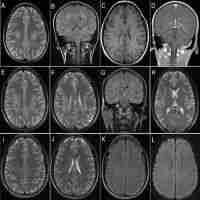

| Abstract | Background Charcot-Marie-Tooth disease (CMT) is a group of single-gene hereditary diseases of peripheral nerve with high clinical variability and genetic heterogeneity. The typical clinical manifestations include progressive muscle weakness and muscle atrophy in the distal extremities, accompanied by disappearance of tendon reflexes and distal sensory disturbances. CMT2A2 (OMIM: 609260) is caused by the mutation of MFN2 (OMIM: 608507), is the most common type of axonal pattern. Although a small number of patients with X-linked CMT1 (CMT1X) present with central nervous system involvement, including reversible white matter lesions, it is rarely in CMT2A2. Case presentation A 3-year and 5-month-old girl had experienced motor lag, muscle tension, and abnormal gait for over a year. A reexamination of cranial MRI revealed an anterior enlargement of the abnormal signal range in the lateral ventricles and bilateral frontal lobes. And the whole exon sequencing showed that this girl carried a heterozygous missense mutation c.314C > T of MNF2 gene, inherited from her mother. Conclusions In this study, we retrospectively analyzed the clinical and molecular genetic findings of a child with Charcot-Marie-Tooth disease A2 with central nervous system involvement as the initial presentation, and explored its pathogenic mechanism. |